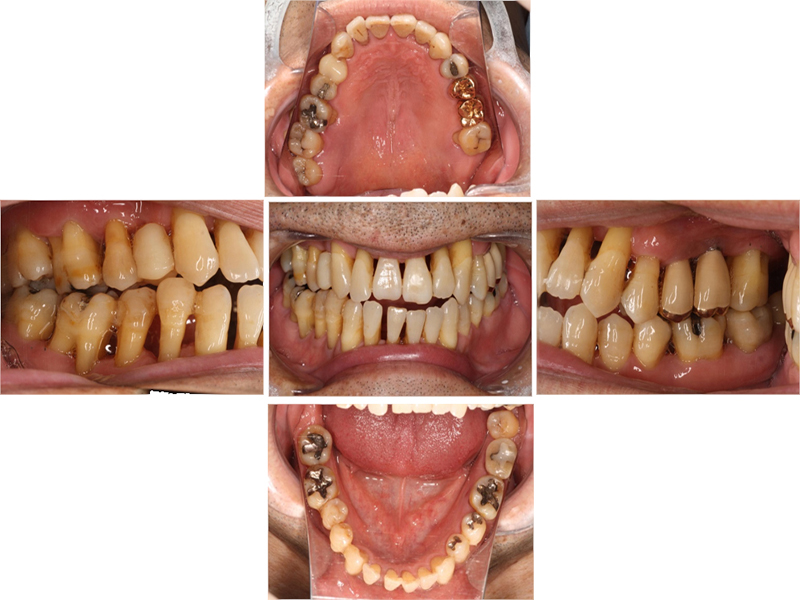

初診時口腔内写真